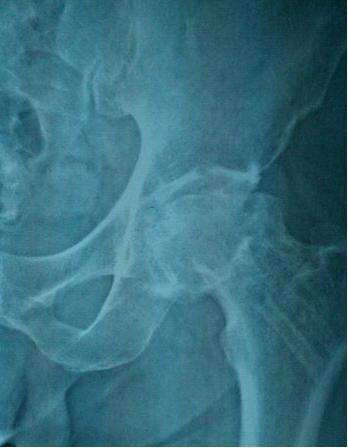

儿童骨头坏死是什么

儿童股骨头坏死,又称股骨头骨骺软骨炎、股骨头无菌性坏死或扁平髋。是儿童常见的原因不明的软骨病,多发于2~12岁儿童,以退行性变或坏死开始,继后出现再生或重新钙化,最终出现股骨头的坏死。一开始表现为膝关节-髋关节痛,步行不便或跛行,患髋不能屈伸、内收。因为有的很隐匿,孩子只是有点疼,跛行两天,有像是没事了,只有磁共振才能发现股骨头的缺血水肿,本病早期诊断早期治疗十分重要,但又有几个家长愿意让孩子因为髋关节有点疼痛就去做磁共振呢?

非手术治疗:非手术治疗主要用于年龄<6岁,CatterallⅠ-Ⅱ型的患儿。方法有卧床休息、外展位牵引、石膏固定、外展支架或矫形器矫正等,这些支具需下肢外展40°-45°,内旋10°-15°或无内旋,以期获得包容,防止脱位。佩戴支具后髋、膝关节可自主活动,这不仅有利于股骨头形态的重塑和保持良好的活动范围,且能促进关节滑液的流动,有利于软骨和滑膜的营养。

手术治疗:手术治疗主要应用于年龄>6~8岁,Catterall II―III期以上、部分Ⅳ期的患儿以及髋关节半脱位、有临床危象征(髋关节疼痛、功能受限)的患儿。近年来随着对该病的进一步认识,多倾向于在疾病的早期即采取积极的手术治疗措施,常用的术式有骨盆截骨术和股骨上端内翻旋转截骨等。而一些可能针对病因治疗的方法,如钻孔减压法降低骨内压,血管植入以增加头骺血循环,滑膜切除以缓解关节填塞等,目前还没有得到大家的公认,且手术效果欠满意。

儿童股骨头坏死没有被正常的治疗或正常的治疗延误以后致残风险是很高的,治疗的预后跟发病的年龄,治疗方式的干预是否恰当,是否及时的是相关的,发病在六七岁以后,及时的进行手术治疗能够有效的避免股骨头发生严重的致残类型,如果已经延误治疗也有一些手术方法,可以把残疾的程度降到最低。